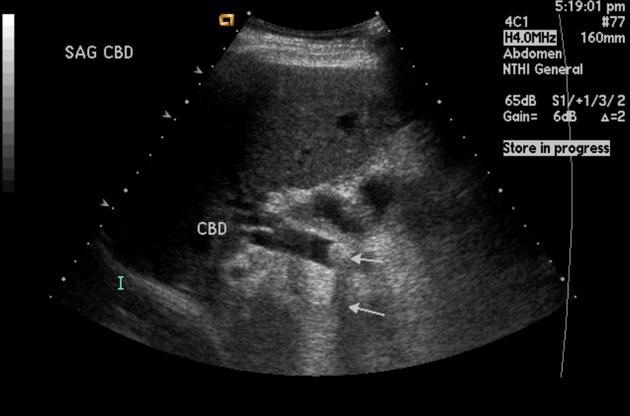

Choledocholithiasis

obstrution by biliary stone

RUQ pain

Fever

Jaundice

Elevated Conjugated bilirubin

Elevated Alkaline phosphatase ALP

Elevated GGT

Elevated amylase and lipase

Elevated white blood count